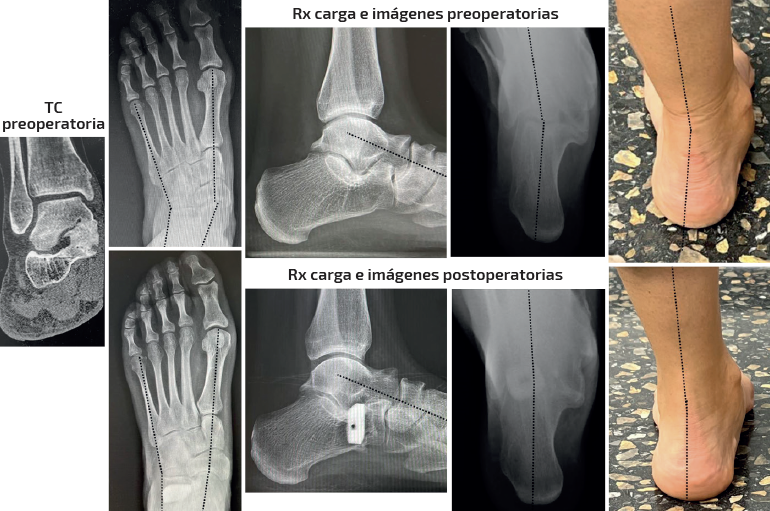

Caso 1 (Figura 4)

Se trata de una paciente mujer de 25 años afecta de dolor medial y sinus tarsi. Antecedente en adolescencia de esguinces laterales frecuentes. Diagnosticada previamente de forma errónea de microinestabilidad de tobillo. Evidencia de coalición ósea talocalcánea en pruebas de imagen y deformidad clínica y radiológica con predominio de abducto. Subtalar rígida. Tipo IIB de Myerson. Tratamiento: osteotomía de alargamiento de la columna externa con cuña de metal trabecular como único gesto quirúrgico. Seguimiento: 2 años. Capaz de caminar largas distancias sin dolor. Mejoría de la alineación clínica y en las radiografías dorsoplantar y de Saltzman. Sin cambios en las ángulos sagitales.